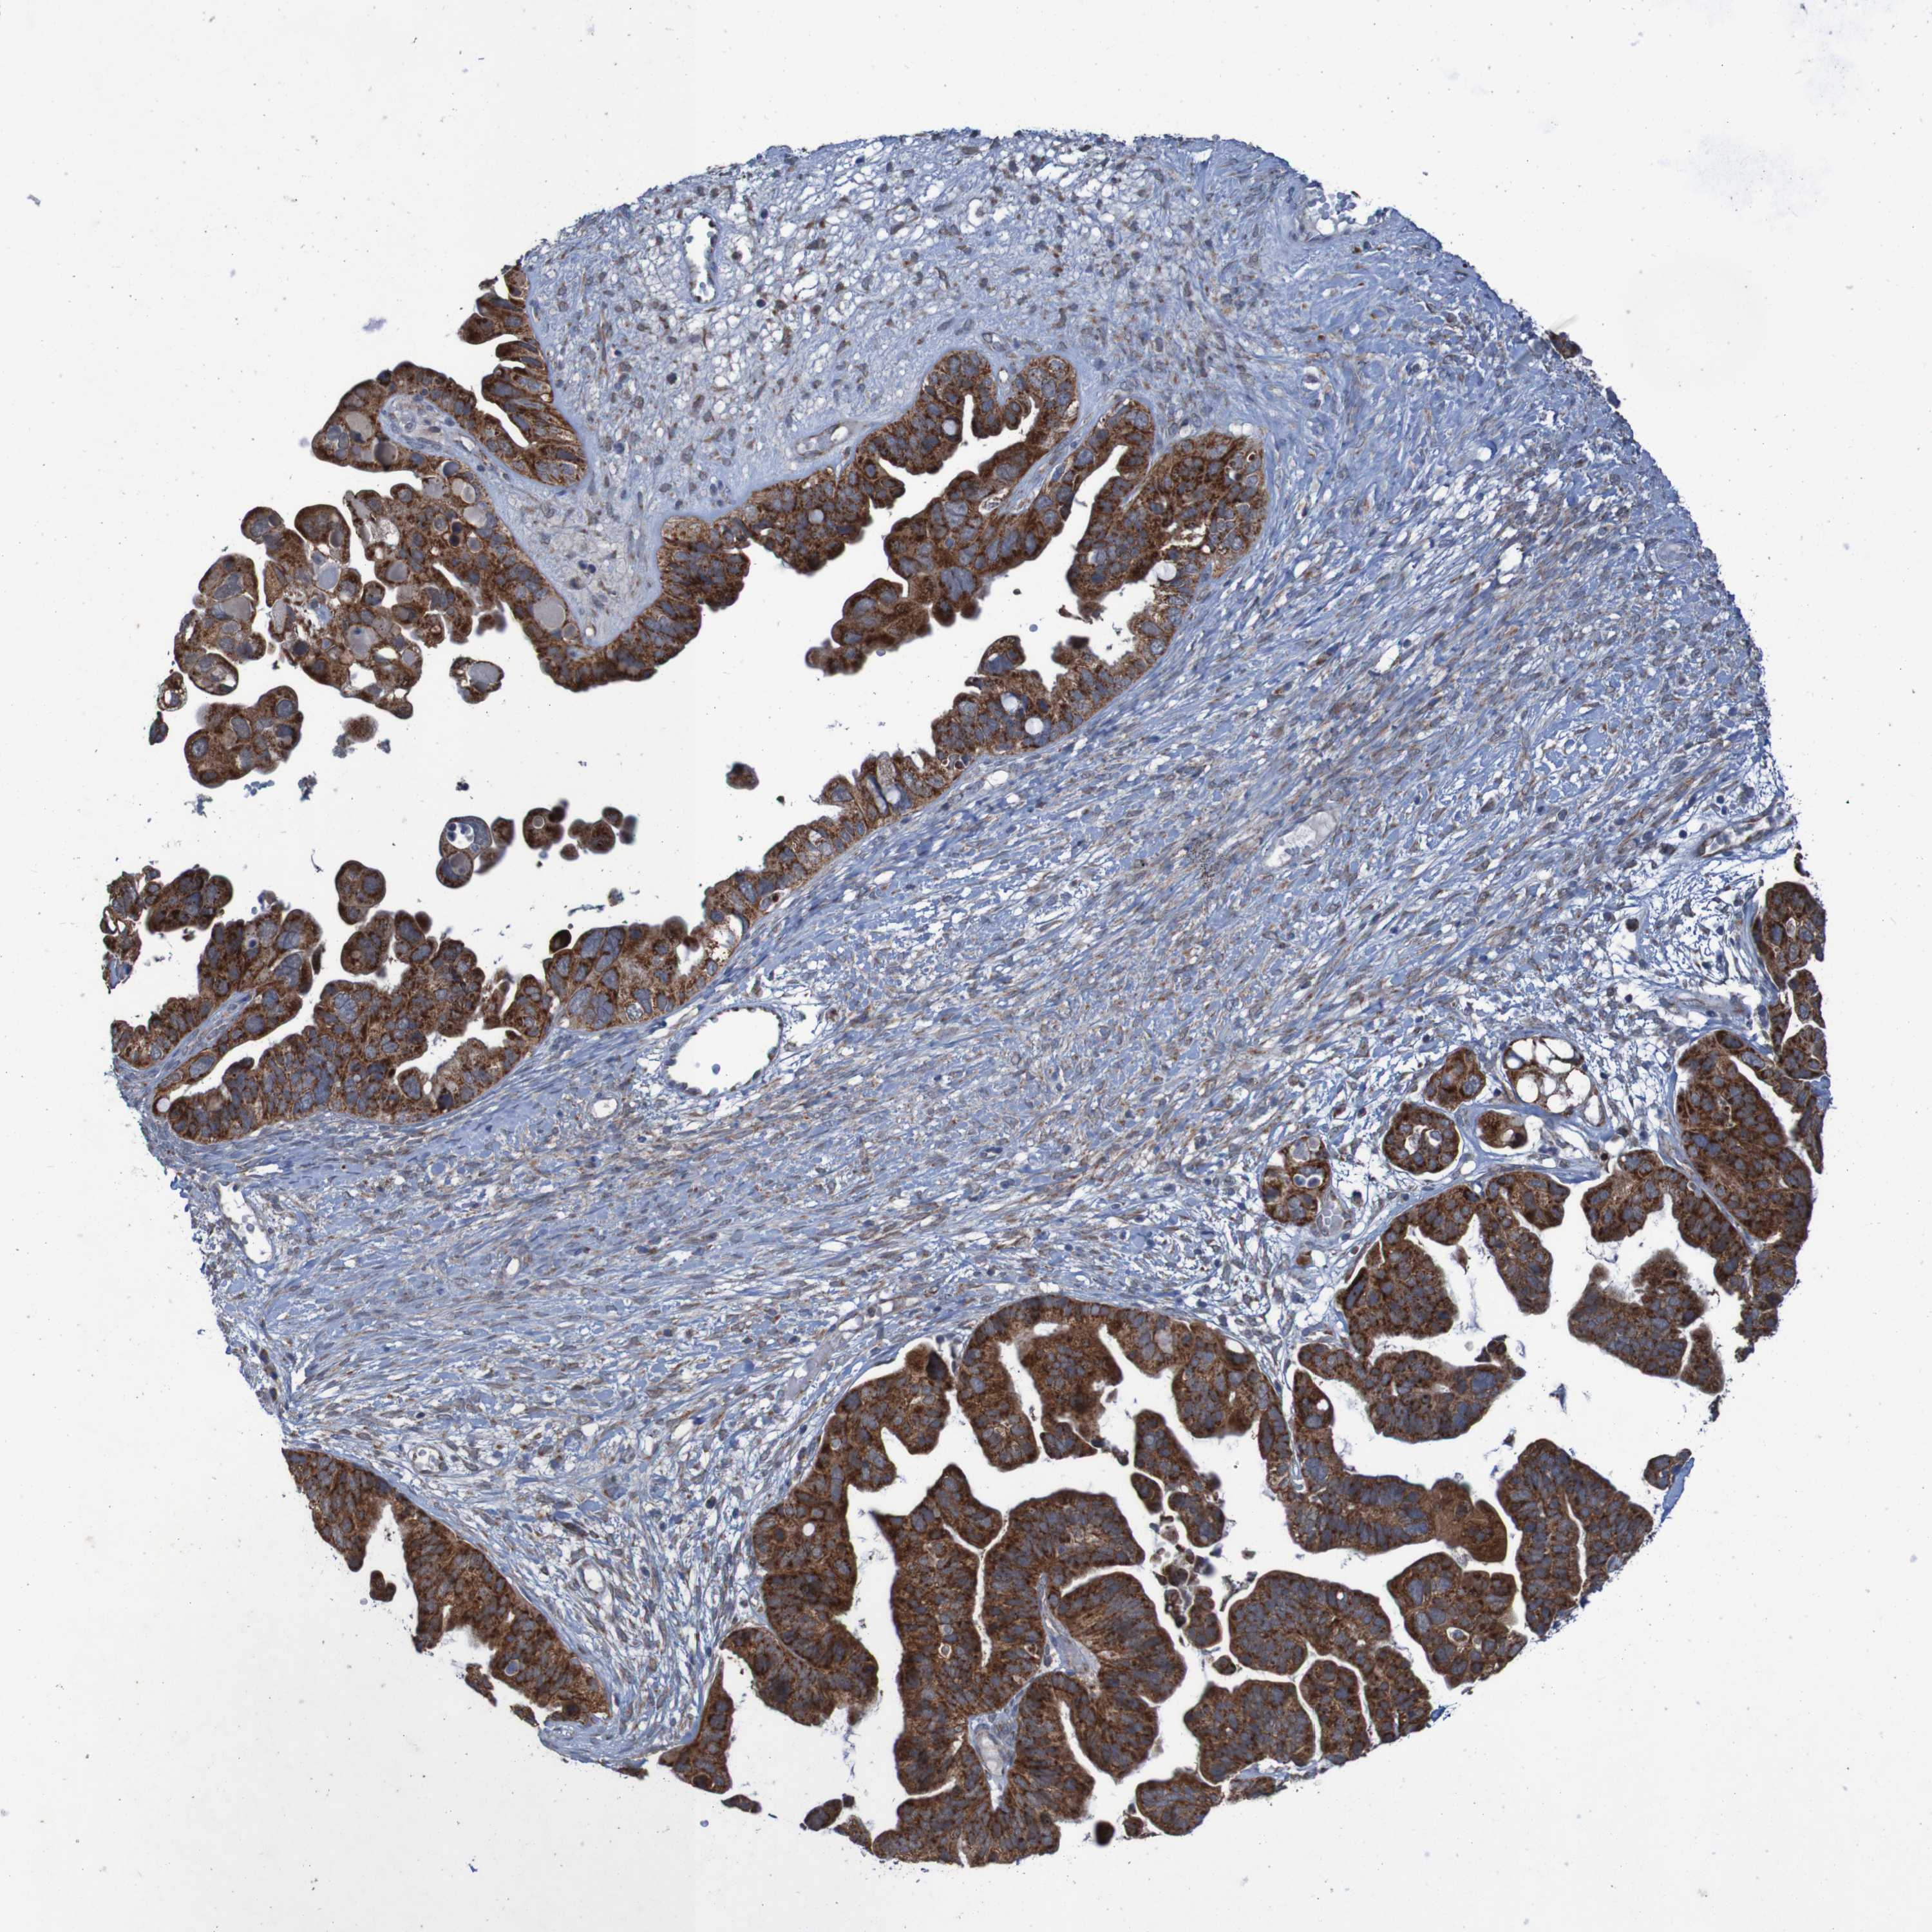

OVARIAN CANCER - Protein expressioni

A mouse-over function shows sample information and annotation data. Click on an image to view it in a full screen mode. Samples can be filtered based on level of antibody staining by selecting one or several of the following categories: high, medium, low and not detected. The assay and annotation is described here.

Note that samples used for immunohistochemistry by the Human Protein Atlas do not correspond to samples in the TCGA dataset.

Antibody stainingi

Antibody staining in the annotated cell types in the current human tissue is reported as not detected, low, medium, or high, based on conventional immunohistochemistry profiling in selected tissues. This score is based on the combination of the staining intensity and fraction of stained cells.

Each image is clickable and will lead to virtual microscopy that enables deeper exploration of all samples and also displays staining intensity scores, fraction scores and subcellular localization as well as patient and tissue information for each sample.

Antibody HPA010980

Antibody HPA011408

Staining

High

Medium

Low

Not detected

Intensity

Strong

Moderate

Weak

Negative

Quantity

>75%

75%-25%

<25%

None

Location

Nuclear

Cytoplasmic/membranous

Cytoplasmic/membranous,nuclear

Cystadenocarcinoma, serous, NOS

Carcinoma, endometroid

Cystadenocarcinoma, mucinous, NOS

Carcinoma, NOS